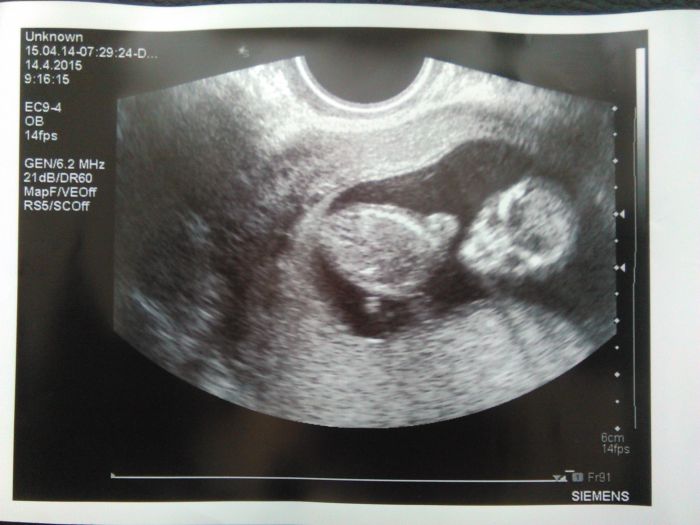

Tak i ja uz mam po screeningu :-) Na vysledky cekam a na krev skocim zitra.. A take mame prvni foktu mimca. Vypada trochu hrozive, jak mimozemstan ;-) Pan doktor povidal, ze se smeje, ale ja nic nevisela. No a poprve jsem byla na jake-koliv kontrole ci vysetreni sama :-( Dceri se chtelo spat, tak zustali s tatkou doma..

[728567] :-D Miru tak fotky ze screeningu mame podobny, moje na ni vypada taky jako mimozemstan :-D je videt ze mame stejnyho doktora :-D....moji mamce jsem tu fotku poslala a ona uz u sebe v praci oznamila ze bude po druhe babickou a ze to zrejme bude mimozemstan :-D